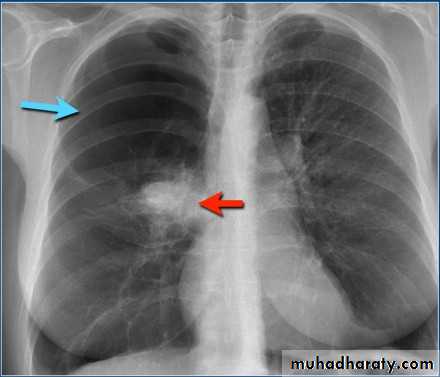

What is the difference?

Differential diagnosis?